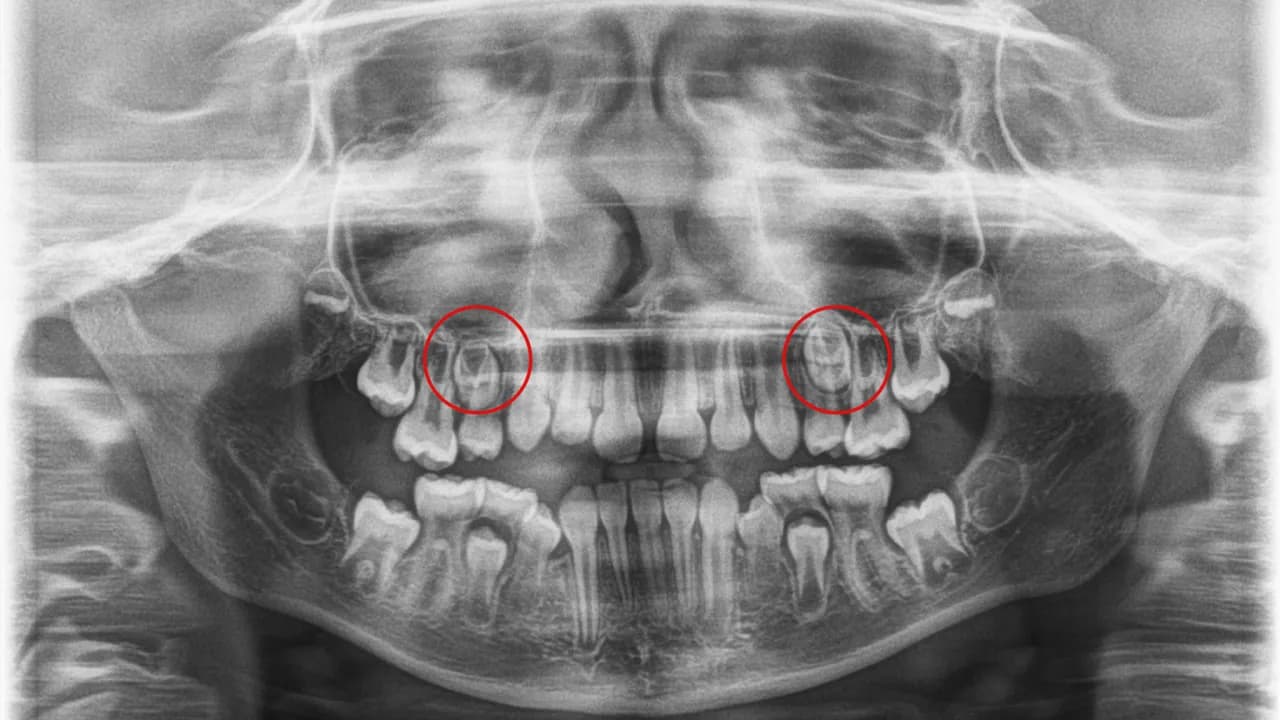

Refundacja pantomogramu przez NFZ dotyczy zarówno dorosłych, jak i dzieci. Dla dorosłych pacjentów, którzy są leczeni endodontycznie lub protetycznie, badanie jest dostępne w ramach gwarantowanych świadczeń. Dzieci i młodzież w wieku od 5 do 18 lat mogą korzystać z pantomogramu bezpłatnie, ale tylko w uzasadnionych medycznie przypadkach, takich jak podejrzenie nieprawidłowości rozwojowych zębów czy zmiany chorobowe w kościach szczęki.